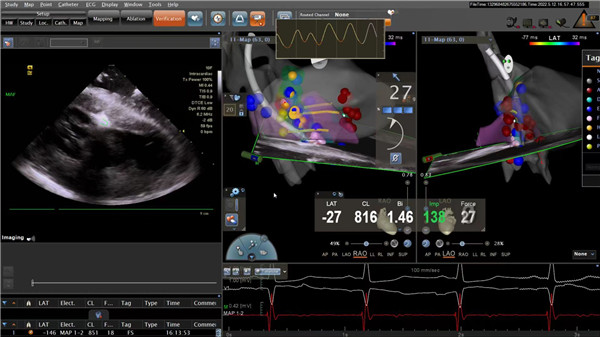

完善相关的术前检查后,王洪涛副主任医师带领蒋伟,孙阳医师、徐凯护师、徐一涛护师等组成的电生理团队为该患者行ICE(心腔内超声)指导下肥厚型心肌病室间隔射频消融术。首先经ICE构建左室及左室流出道解剖模型,并构建室间隔与二尖瓣叶前向运动接触区域(SAM征),拟为消融靶点。随后经股动脉鞘管送猪尾导管分别置于主动脉瓣上、瓣下,测术前主动脉瓣内压力68mmHg, 左室内压力95mmHg,压力差27mmHg。撤出猪尾导管,经股动脉鞘管送ST消融大头至左室间隔面,标测His及束支电位后,定位大头至室间隔最厚部位,功率35-55W放电消融,可见局部组织明确水肿,瘢痕挛缩。消融结束,再次经猪尾导管测量术后主动脉瓣内压力131mmHg,左室内压137mmHg,压力差6mmHg。术后裴女士未再发作心绞痛症状,胸闷、气短明显减轻。术后复查心脏彩超示左室流出道梗阻明显改善,康复出院。

ICE指导下室间隔射频消融术